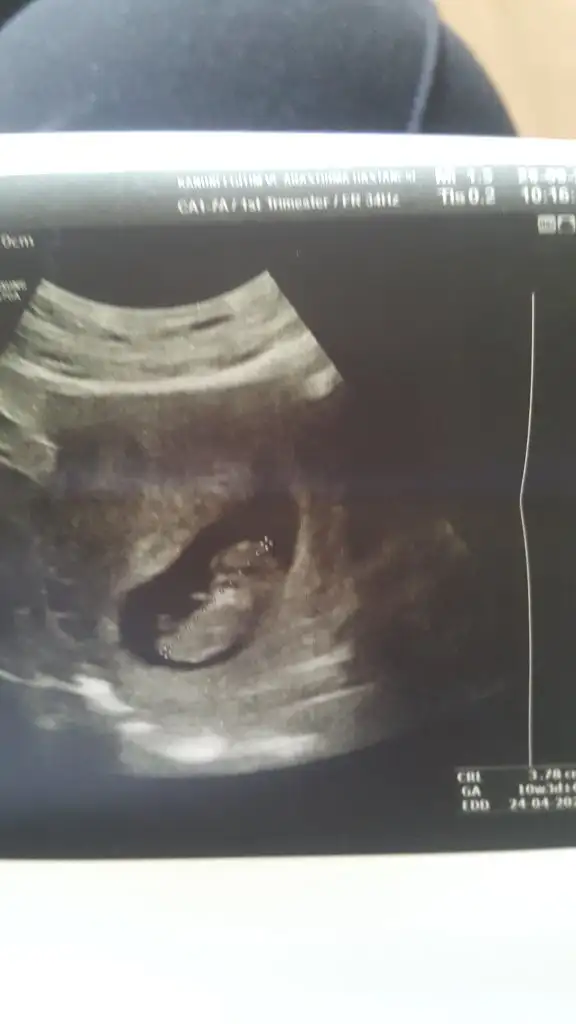

Merhaba Nub için erken ama ramziye tahminde bulunur musunuz 6 haftalık karından ☺️